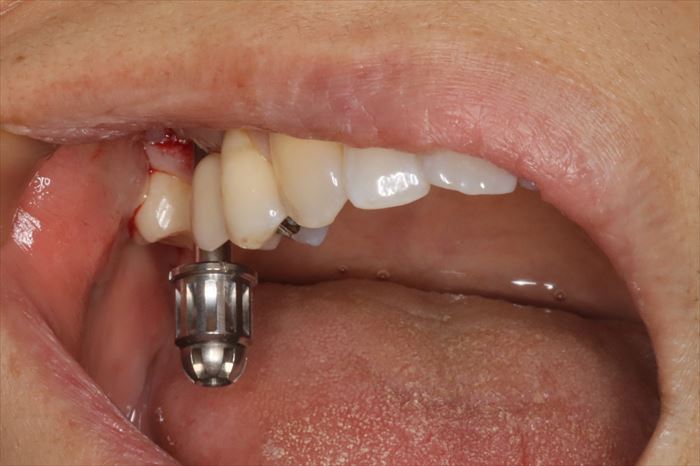

N・Hさんの右上第一大臼歯部分(6┘:右上6)のインプラントの再治療を行います。(矢印)

咬合面のスクリューを緩め、まずは被せ物(クラウン)を取り外しました。

インプラント本体が理想的な位置よりも頬側に存在していることがわかります。

アバットメント(中継ぎパーツ)を取り外しました。